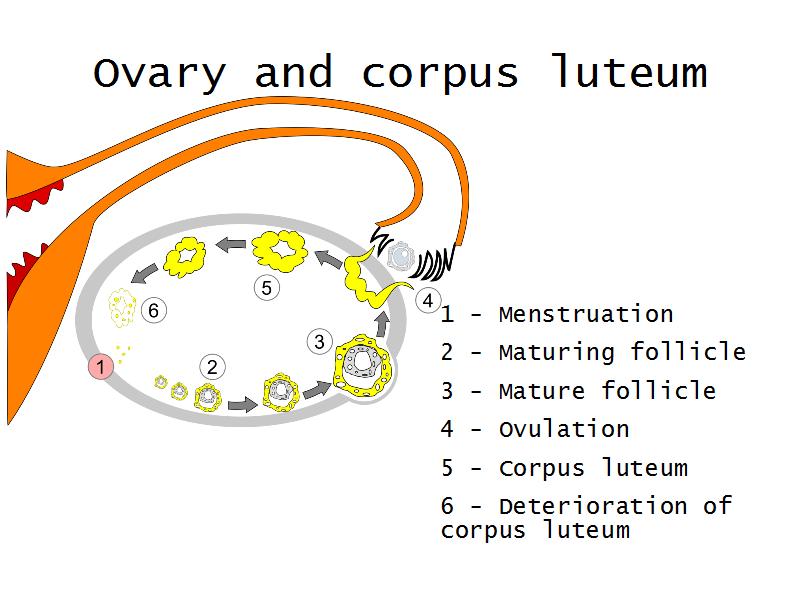

- Ovary

- Corpus luteum

- F3: Granulosa cell

- F3: Granulosa cell = ovarian follicle

- Slide 89/106: Ovary

- Slide 91: Corpus luteum